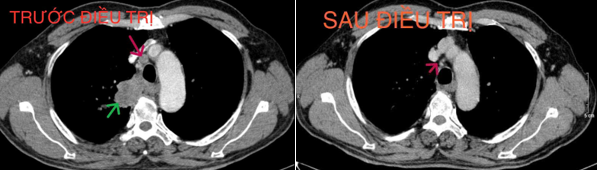

+ Chụp cắt lớp vi tính lồng ngực (16/12/2024): Hình ảnh cấu trúc dạng hang thùy trên phổi phải, kích thước ~36x22x44mm, bờ không đều, thành dày không đều, ngấm thuốc không đồng nhất sau tiêm. Hạch trung thất và rốn phổi phải.

Hình 6. Khối u trước và sau điều trị (mũi tên xanh), sau điều trị kích thước khối u giảm còn khoảng 36x22x44mm

Hình 7. Hạch trung thất trước và sau điều trị (mũi tên xanh), kích thước hạch sau điều trị giảm xuống còn dưới 10mm đường kính trục ngắn.

*Kết luận: Ca lâm sàng trên cho thấy một trường hợp bệnh nhân nam lớn tuổi, chỉ số toàn trạng (Performance Status - PS) 1, vào viện với tình trạng khó thở và đau ngực nhiều, được chẩn đoán Ung thư phổi không tế bào nhỏ giai đoạn IIIB. Sau 4 chu kỳ hóa trị liệu với phác đồ Docetaxel - Carboplatin, bệnh nhân đạt được đáp ứng bệnh một phần, khối u giảm khoảng 50% kích thước so với trước khi điều trị, kích thước hạch trung thất giảm và nhiều hạch không còn nhìn thấy trên phim chụp cắt lớp vi tính. Sau điều trị bệnh nhân hết các triệu chứng lâm sàng, thể trạng được cải thiện và sinh hoạt trở lại bình thường. Bệnh nhân tiếp tục được đánh giá lên kế hoạch điều trị tiếp theo.